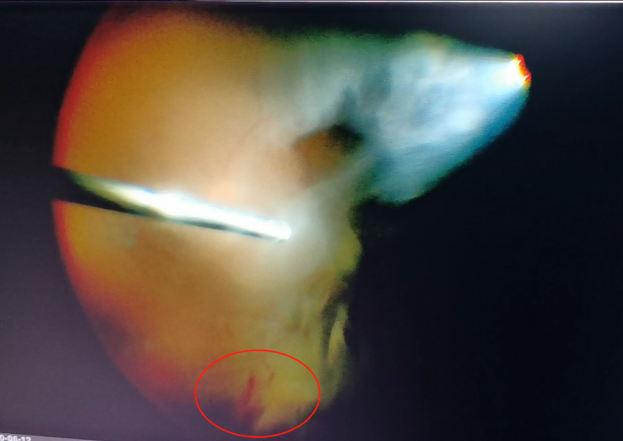

手術中,醫(yī)生們先后為程先生行白內(nèi)障超聲乳化術及后入路玻璃體切割術,并置入人工晶體。手術僅用半個小時便順利完成。

(左為玻璃體切割術中,明顯可見有積血;右為激光治療后的眼底)